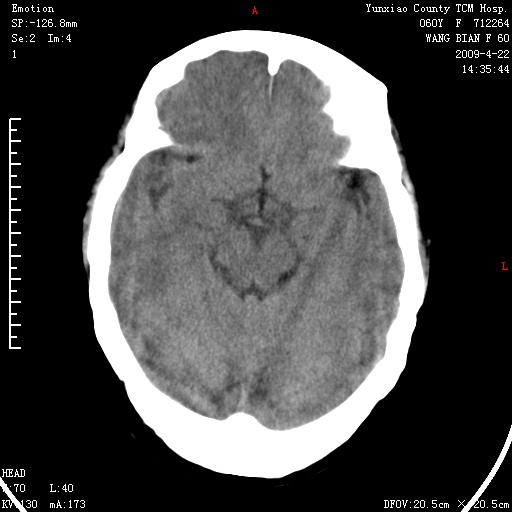

标题: CT19525:体检

1、头颅未见明显异常。

2、左肾囊肿。

1、头颅未见明显异常。2、左肾囊肿可能。建议增强

1、枕骨蛛网膜粒压迹。2、左肾囊肿可能。建议增强

头颅未见明显异常。左肾囊肿。

1)枕骨蛛网膜粒压迹。2)左肾囊肿可能。

2、左肾囊肿可能性大。